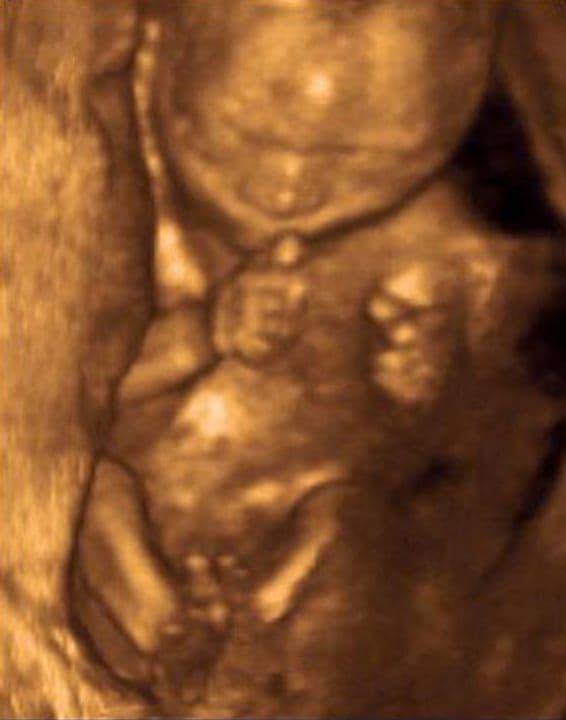

20 Weeks 5 Days Pregnant

In 20 weeks and 5 days pregnancy, the skin is less translucent now as your baby is starting to lay down fat stores, which after the birth will help with temperature control and provide an energy reservoir for your baby to call upon when necessary. Your developing baby is becoming more responsive and aware every day as his nervous system begins to work more effectively.